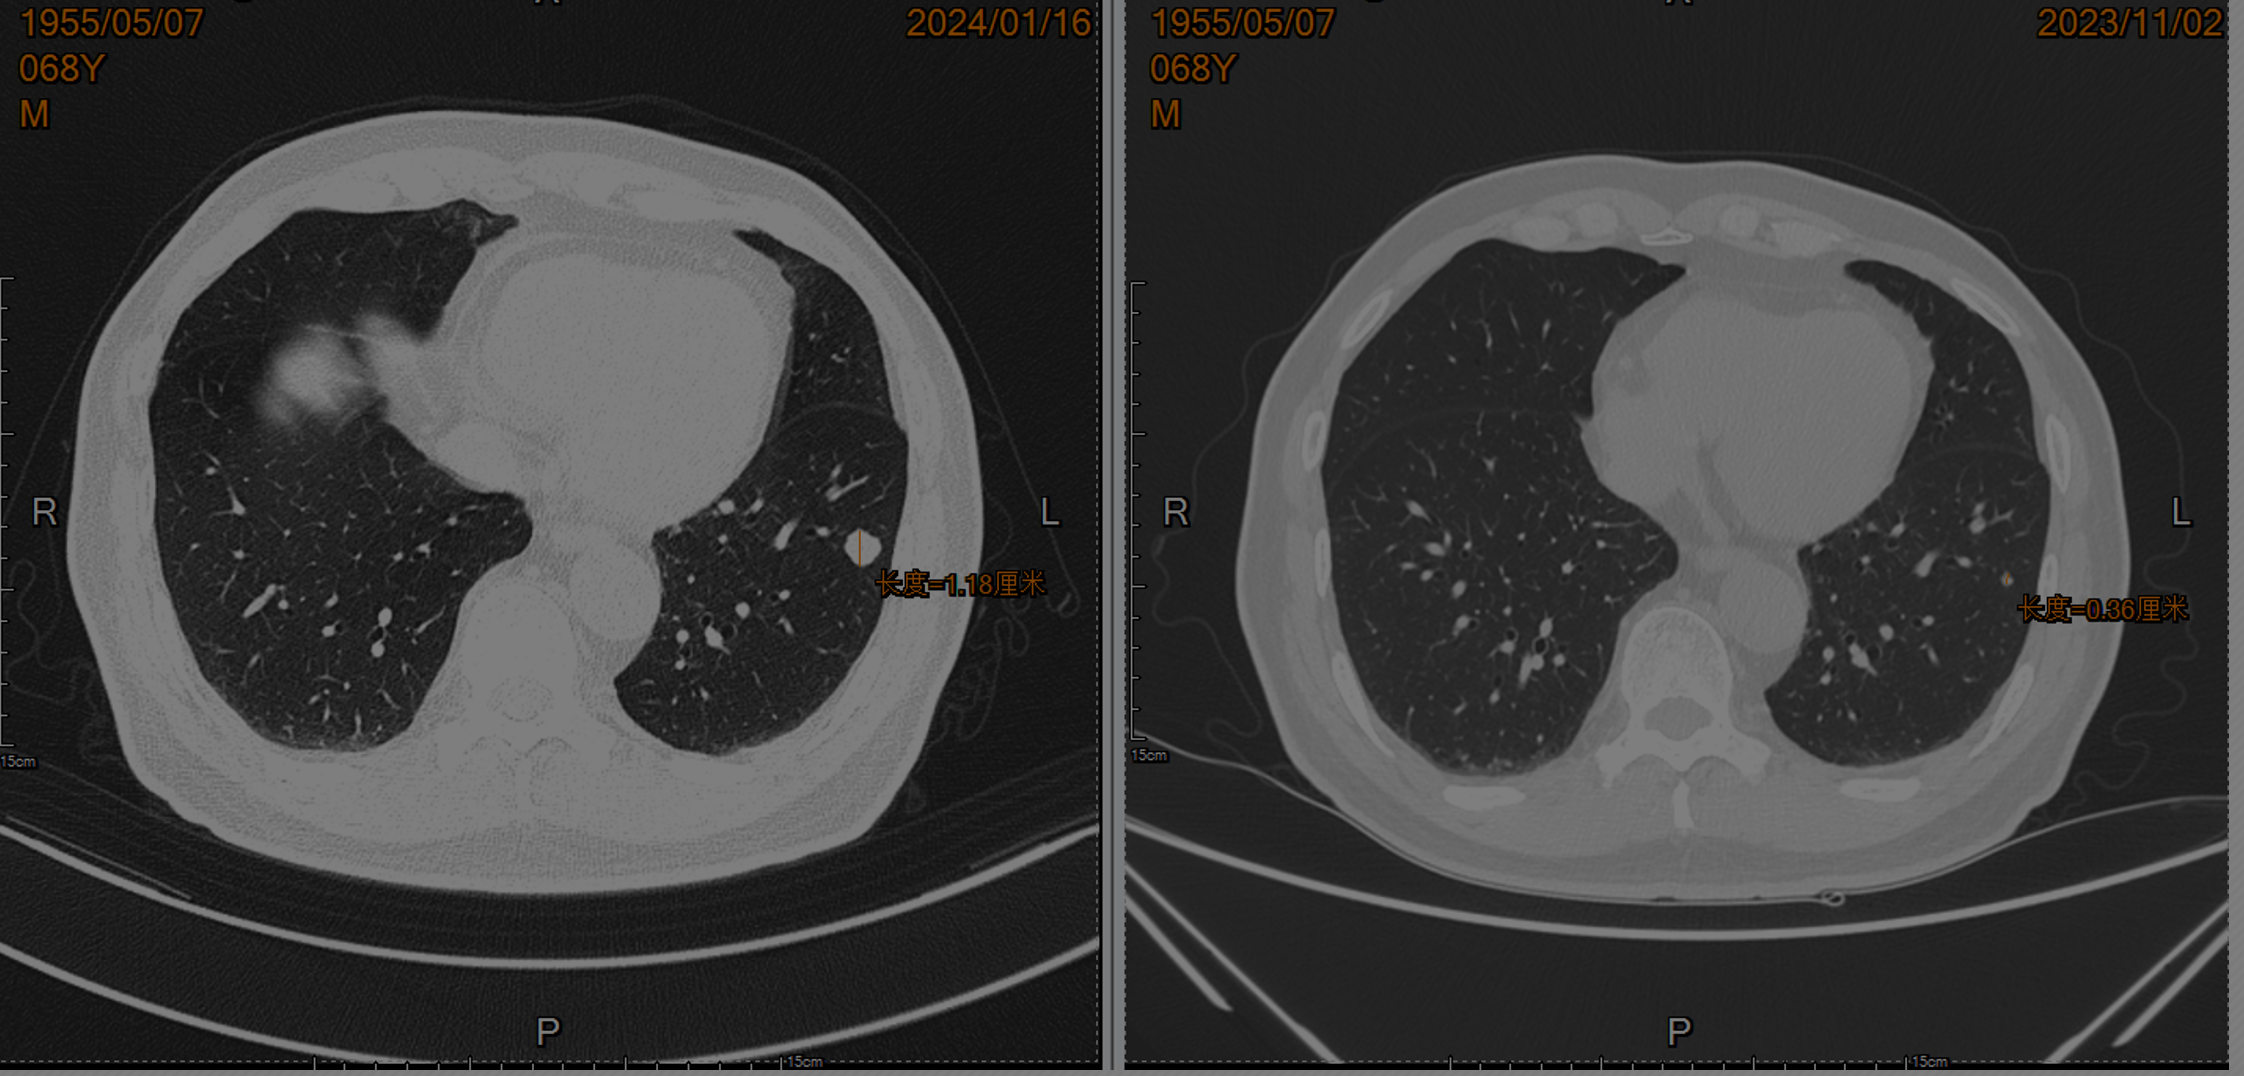

• 2024.01复查肺CT:双肺肺内可见多处小结节影,大者直径约为11mm,考虑转移瘤可能。余脑/骨/全腹盆腔未见明确复发转移

• 2024.01予以“培唑帕尼200mg qd”靶向治疗;2024.03加量至“培唑帕尼400mg qd”靶向治疗

• 2024.3、2024.6复查:双肺肺内可见多处小结节影,部分缩小,部分结节内空洞形成。

• 2024.10复查疾病进展并出现骨转移,考虑患者不规则用药,予重新恢复口服培唑帕尼,并加量至600mg qd。

• 2024.12培唑帕尼加量至800mg qd,监测血压波动在125-156/81-101mmHg间,每日解2-3次稀糊样便,药物控制不佳,改“培唑帕尼800mg qd”维持至今,期间疗效评价SD,未见颅内转移。

• 目前患者通过培唑帕尼一线靶向治疗已超两年,获益明确。